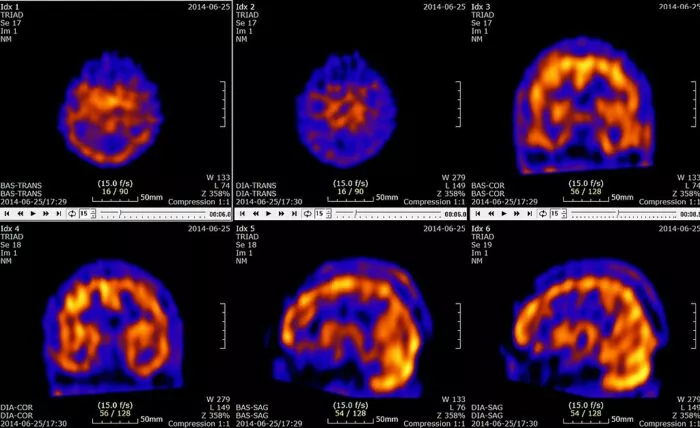

Radionuklide, die in der Regel durch eine Injektion in die Vene verabreicht werden, senden Strahlung aus, die von Geräten erfasst und zu einem 3D-Modell zusammengesetzt wird. Zu diesem Zweck werden unter anderem Technetium-99-Isotope für die SPECT-Diagnostik (Single-Photon-Emissions-Computertomographie) oder Fluor-18 für die PET-Diagnostik (Positronen-Emissions-Tomographie) verwendet.

Technetium-99 wird unter anderem für spezielle CT-Scans des Gehirns verwendet.